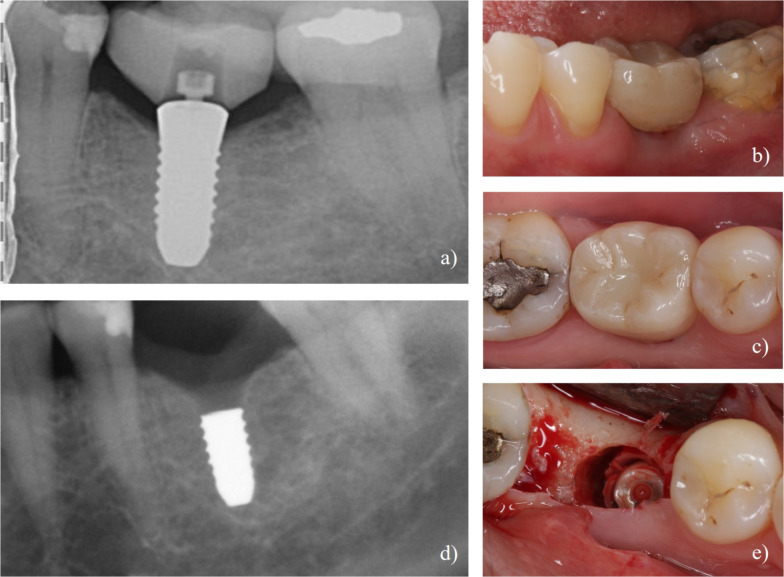

Methods: Twenty-four patients received single two-piece zirconia implants (CERALOG® Hexalobe) in healed sites. After a 6-month healing period, implants received provisional screw-retained crowns on PEKK temporary abutments, followed by definitive lithium disilicate crowns (IPS e.max Press) on PEKK abutments. Clinical and radiographic examinations were performed at implant placement, re-entry, definitive loading, and 12-month follow-up, along with patient-reported outcome measures.

Results: The implant survival rate at 12 months was 60.9%. Nine implants were lost: two due to lack of osseointegration at re-entry, four due to mobility after loading, and three due to fractures in the coronal third after loading. Surviving implants showed stable soft tissue parameters with mean probing pocket depths of 2.7 ± 0.7 mm at 12 months. The mean distance from implant shoulder to first bone contact decreased from 1.9 ± 0.6 mm at loading to 1.4 ± 0.6 mm at 12 months. Patients with surviving implants reported high satisfaction scores (4.8 ± 0.4) for function and aesthetics.